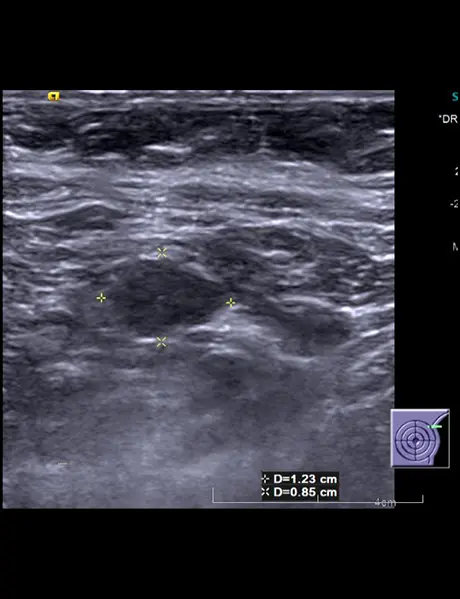

Left breast USG showing mass forming area consisting of multiple thickened dilated ducts extending into the subcutaneous region (straight white arrow). There is parenchymal edema surrounding this area of abnormality.

Multiple enlarged lymph nodes with thickened cortices and loss of fatty hilum in left axilla .